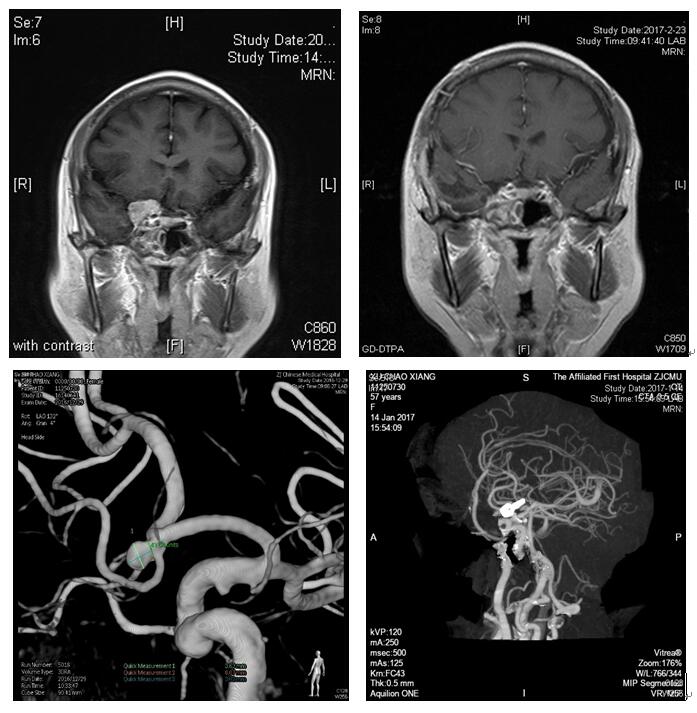

日前,一位蝶骨嵴内侧脑膜瘤术后患者特意来向神经外科竺国充和徐震副主任医师表示感谢,而术后影像学复查也再次证实了手术的良好效果。

神经外科表示,近年来随着我院神经外科手术技术的发展成熟,先进设备的引进,我们自行开展的高难度手术越来越多。近期来,我科已连续开展多例蝶骨嵴内侧脑膜瘤切除术,前交通动脉瘤夹闭术及桥小脑角肿瘤切除术等,均取得了满意的效果。

这些手术都属于前颅底和后颅底的范畴,解剖复杂,血管神经丰富,操作腔隙小,容易出现并发症或者病灶的残留,需要扎实的显微神经解剖知识和显微外科技术,历来是神经外科的难点。

目前,我院颅底显微外科技术已走向常规化,效果也十分不错,这也标志着我院神经外科技术迈上了一个新的台阶,能为更多患者带来福音。